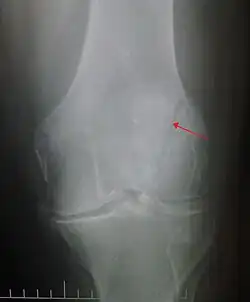

Some people have a normal bipartite patella or two-part patella which can appear as a fracture. The fragment is usually seen in the top outer corner of the patella and can be distinguished from a fracture by being present in both knees.[6]

Differential diagnosis